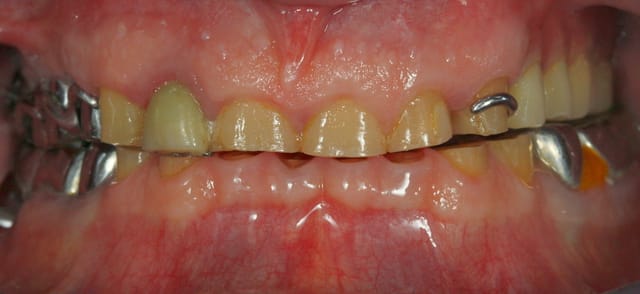

Tout d'abord il faut fixer des nouveaux repères:

- repère esthétique, où doit se situer le bord libre des incisives, par rapport au sourire. En fonction de ce bord libre et de la forme qu'on veut donner aux dents, on va déterminer si il faut rallonger le dents par le bas, ou par le haut (élongation)

- Repère de dimension verticale. En fonction de l'arcade du haut, où va t'on placer l'arcade du bas. A valider esthétiquement et fonctionnellement.

En fonction après je partirais sur des couronnes sur dent vivantes, et implant en postérieur....

Un cas à propos pour illustrer ...

Le traitement est pas fini, je viens de déposer le bridge metal sect 4, 46 a extraire....

et 15 est sous provisoire (prb endo)

Emax pour unitaire (43 44 33 34, bloc antérieur maxillaire) et ccm pour les bridges sur implants

SInus a gauche, et élongation coronaire sur 33 34 43 44, ex de 31 32 41 42 et implant en 42 32.

Le bridge sect 4 j'avais prévu de pas y toucher dans un premier temps. Mais comme ça s'est infécté en cours de route, j'ai fini le maxillaire et on s'attaque au sect 4

Photo interessante de simulation de l'epaisseur / longueur de materiau a rajouter

sur la 1ere photo , on voit un diasystème entre les centrales ,bon OK le bonheur n'est pas loin .

Mais sur la latérale ( 22 ) on voit aussi un diasteme , là ça en fait beaucoup de bonheur , pour une seule personne . Alors quand il y a embrouille sur une latérale du haut , il faut systématiquement aller voir au fond du coté opposé , sans même réfléchir . On va voir , et là , hop là il y a une méga interférence molaire sur 47-17 .

donc rien que là ,avant même de s'exciter sur le décalage inter incisif , de l'occlusion inverse ,et du blocage sur la 34 , on peut en déduire que l'on ne peut enregistrer une centrée mais juste enregistrer la latérodeviation donc l'oim pathologique tellement la 17 interfère.

Voilà pourquoi , il faut avant tout racler à mort les 2 dents du fond , pour savoir si par chance la latéro déviation irréversible ou pas , cad si elle existe en centrée ou pas .

Tu comprends bien que , si sur ton montage , la centée est pipée , le montage ne sert à pas grand chose : tant que l'articulateur est fermé , ce n'est pas grave , mais dès que tu l'ouvre ,là ç est un drame .du coup ton wax-up ne sert plus a rien .C' est quoi déjà ton problème , de savoir si tu fais des facettes ou des couronnes ?:-),il va d'abord faloir determiner la forme des dents .